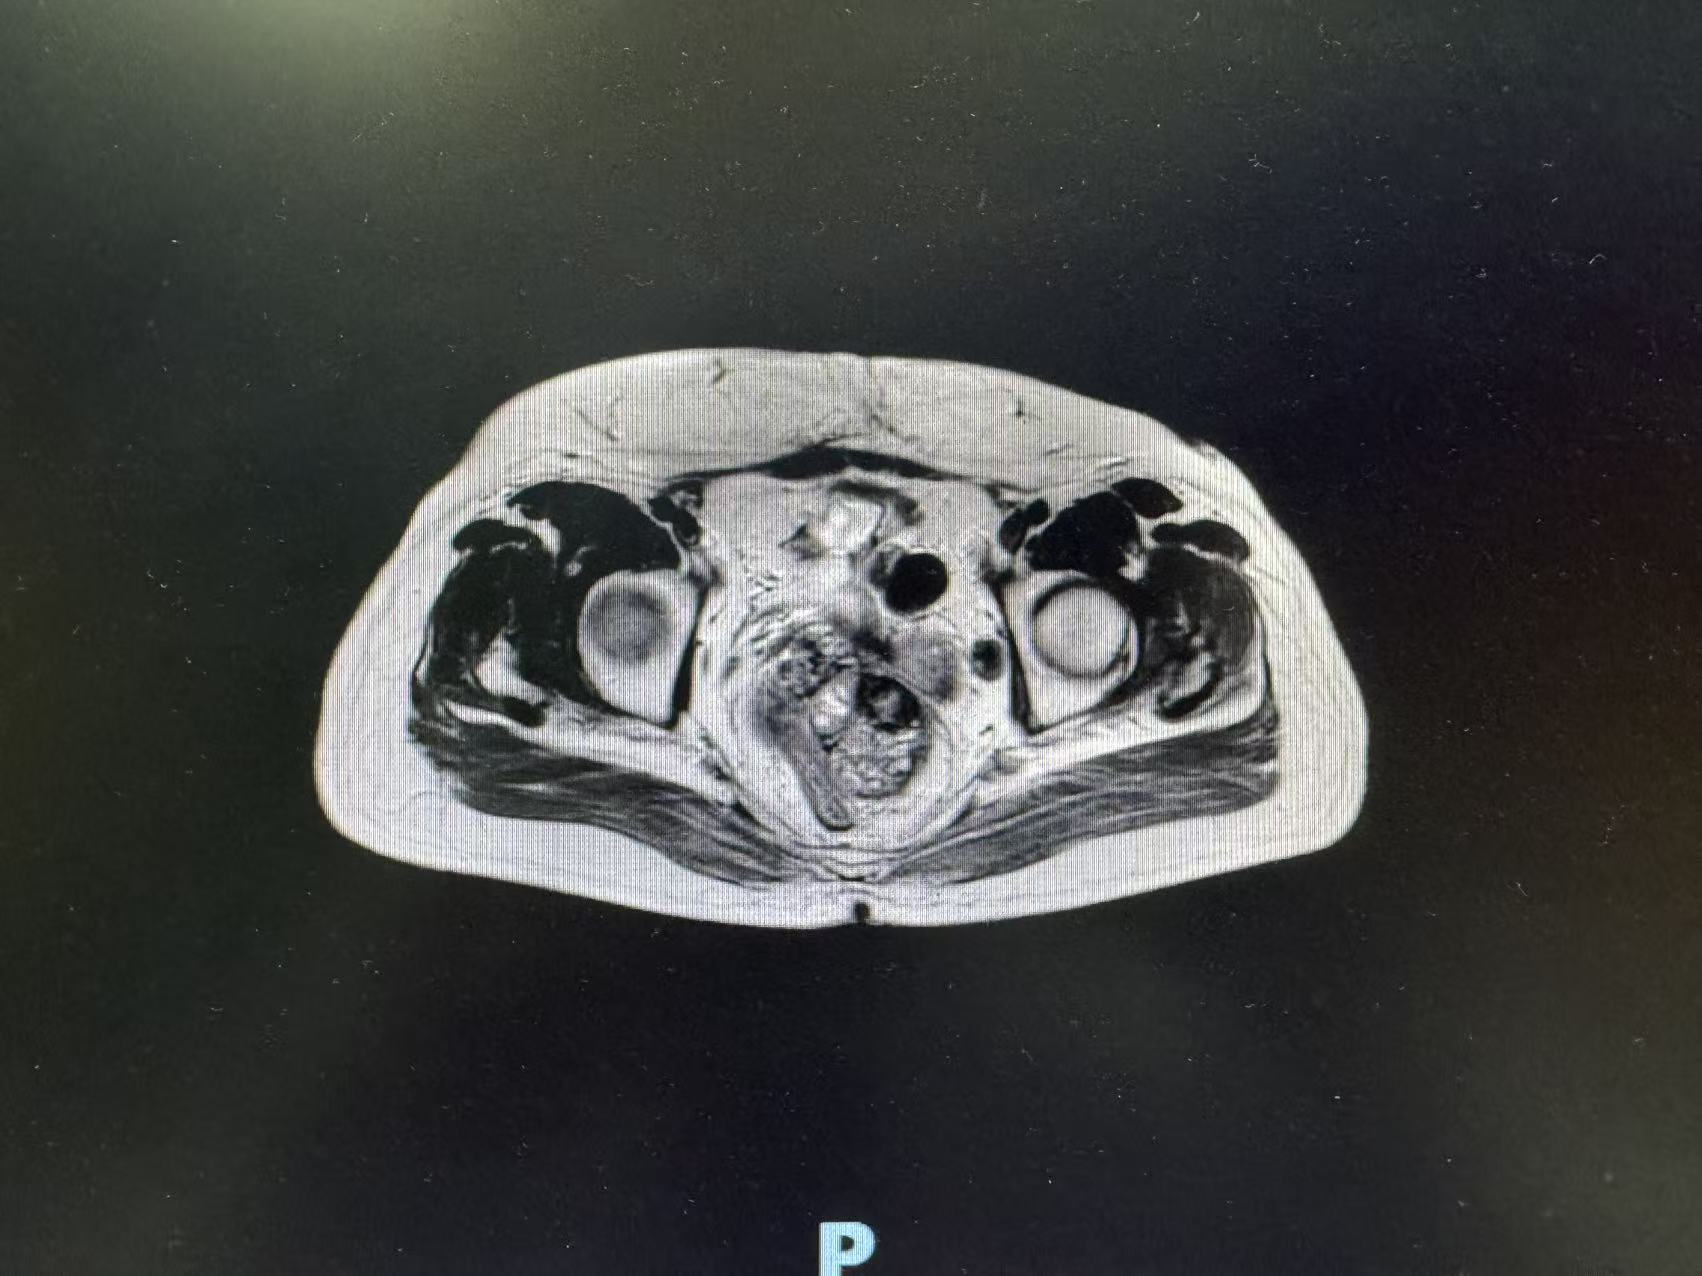

术前肿瘤影像数据

入院后,张玉宝教授立即带领团队对患者病情进行全面细致评估,启动多学科会诊(MDT),联合影像中心、麻醉科、重症医学科等专家,精准研判肿瘤侵犯范围、血管受累程度及脏器功能状态。结合二次开腹手术的特殊性,团队反复优化手术入路与切除策略,充分预判术中可能出现的致命风险,制定周密的个体化手术方案与应急预案,为手术安全筑牢坚实基础。